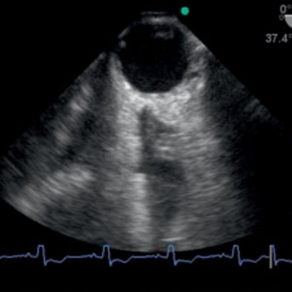

Once regarded as a tool only for the CV ICU, the reliability, image clarity and ease of imaging of TEE is now being put to use increasingly in the general ICU. As critical care echo becomes the dominant means through which intensivists diagnose and manage shock states, TEE offers many advantages over TTE and is an evolving tool in the intensivist’s tool kit. In this unique hands-on workshop, using high-fidelity simulators, image interpretation sessions using actual cases and lectures from leaders in this nascent field, participants will be able to participate in the cognitive and procedural aspects of critical care TEE for the generally ICU patient.